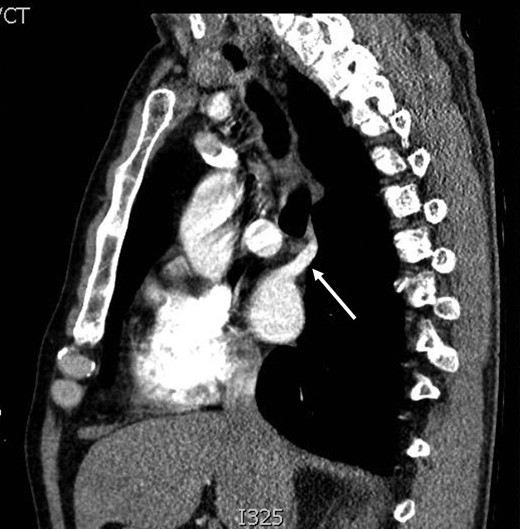

During discussions at the multidisciplinary team meeting, the computed tomography scans of his thorax were reviewed by our radiology colleagues and an anomalous right upper lobe vein was identified.

The patient underwent a right postero-lateral thoracotomy. The right upper lobe pulmonary artery and vein were identified and divided with vascular Endo GIA™ staples. Lymphadenectomy was performed in the draining lymph nodes and we proceeded to isolate the upper lobe bronchus. Prior knowledge of an anomalous venous drainage of the upper lobe made us adopt a cautious approach during dissection posterior to the right upper lobe bronchus and a vascular structure was identified that could be traced in the left atrium; thus, it was found to be an anomalous upper lobe pulmonary vein. The anomalous vein was divided with vascular Endo GIA™ staples. The bronchus was divided with a TA™ stapler.

The patient recovered well postoperatively and was discharged home. Histologically, the patient's tumour stage was pT1aN0 (Figs 1–6).

Kim et al. [2] first reported the contrast-enhanced computed tomography findings of aberrant pulmonary veins, which were observed as a focal nodularity attached to the posterior wall of the bronchus intermedius. Pulmonary vein variations are usually seen in the common pulmonary vein and the middle lobe vein draining into the inferior pulmonary vein or the left atrium [3]. There are only a few CT studies of the upper lobe vein. The frequency is reported between 1.7 and 5.7% [3].

Kim et al. [2] eluded that in 5% of normal subjects, the right superior segmental pulmonary veins had an aberrant course also either to the inferior pulmonary vein or directly to the left atrium. Asai et al. [4] noted that in right lung resection surgeries, there was a 5.7% occurrence of abnormal right upper lobe venous drainage.

Recent advances in non-invasive imaging methods such as multi-detector computed tomography and magnetic resonance angiography have facilitated the detection of pulmonary vessels [4]. Watanabe et al. and Usami et al. reported that three-dimensional CT angiography is a far less invasive and an easier method for delineation of pulmonary vessels than conventional pulmonary angiography prior to lung resection [1].